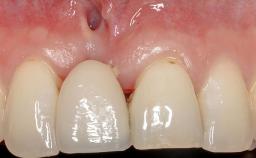

Periodontal Plastic Surgery and Prosthetic Procedures to Treat Peri-Implant Soft-Tissue Dehiscences

A 30-year-old woman was referred by her general dentist for evaluation of an esthetic complication related to previous implant treatment for congenitally missing maxillary lateral incisors. The patient’s chief complaint was the inadequate esthetic appearance of her smile. The case demonstrates the use of a combined approach to achieve optimal results. Two different flap designs - a tunnel technique and a coronally advanced flap - are employed based on the surgical objectives for the affected site.